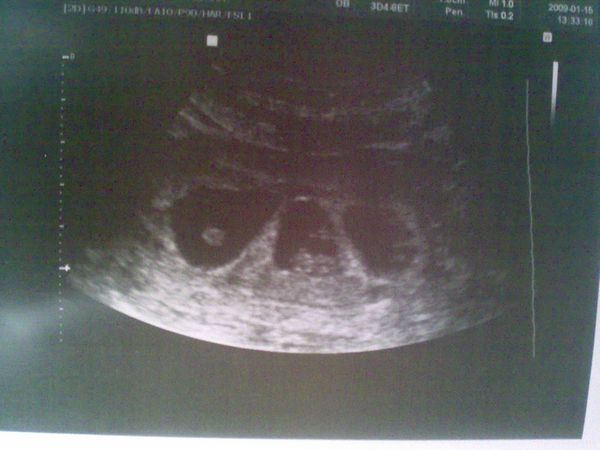

Na,itt vannak ők. :D Jól vannak,9,5 mm-sek,egyik picit kissebb,de jól vannak.Hasi uhu volt,a 4D-sek csinálták.Talán utoljára láttszódnak egy képen,lassan kinövik:

Kép